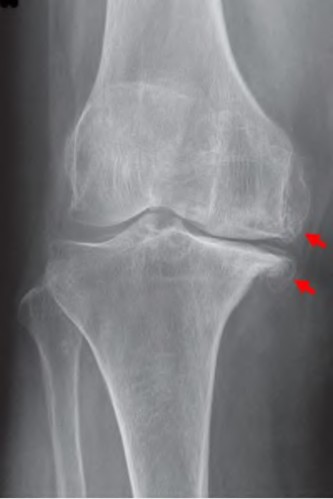

During a posterior-stabilized total knee arthroplasty, the surgeon assesses the gaps with trial components. The knee has a symmetric extension gap that accepts a 10 mm spacer block perfectly. In flexion, the gap is asymmetric, being tight medially and loose laterally. Which of the following is the most appropriate next step in management?

During a revision total knee arthroplasty, removal of the tibial component reveals a massive contained metaphyseal defect measuring 3 cm deep, but with an intact cortical rim. According to the Anderson Orthopaedic Research Institute (AORI) classification, what type of defect is this, and what is the preferred method of management?

During a primary total knee arthroplasty for a severe fixed valgus deformity, the knee is noted to be tight in extension but balanced in flexion. Which of the following lateral structures should be released first to selectively correct the tight extension gap?

During TKA, joint line restoration is critical for proper biomechanics. Which of the following is a direct consequence of inadvertently elevating the joint line by more than 8 mm?